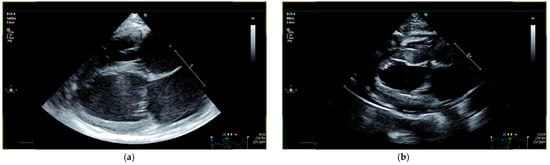

3.1. Cardiac Findings